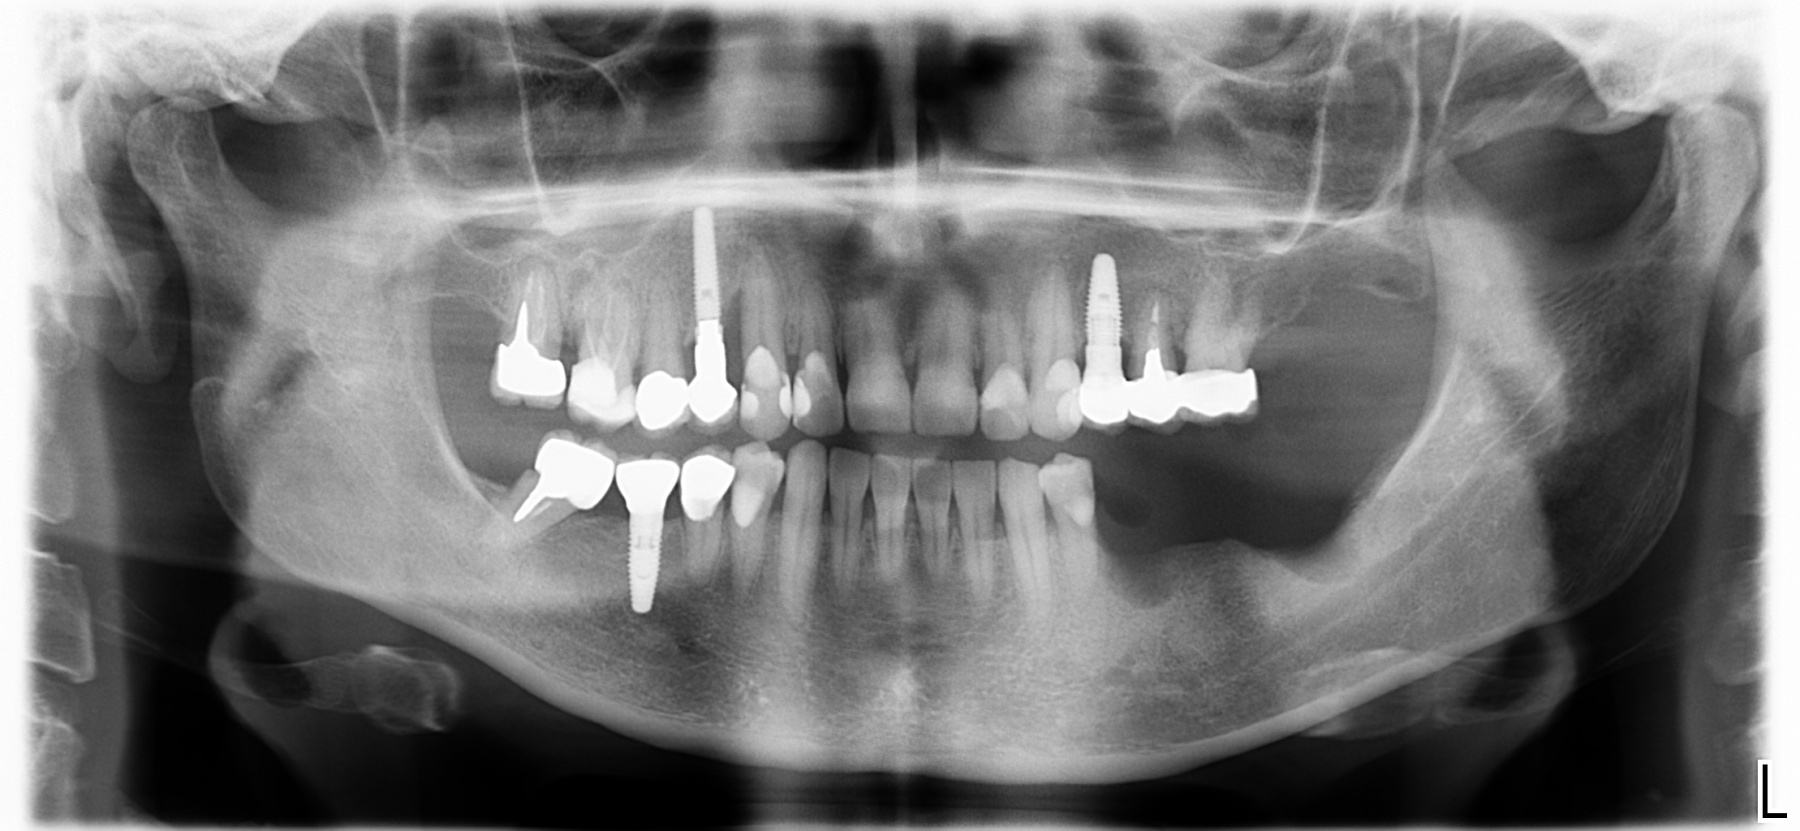

Il nostro studio è inoltre dotato di un a unità radiografica modernissima che permette di eseguire:

• radiografie panoramiche

• teleradiografie

• Tac 3D (tecnologia Cone-Beam)